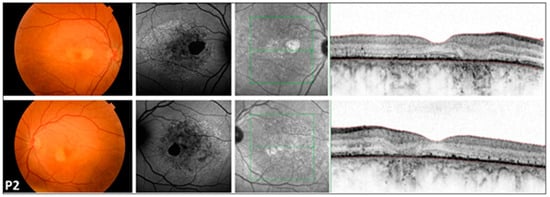

Figure 1. Multimodal imaging of the 46-year-old COD patient (P2) with central involvement. Images of both eyes (right in the superior, left in the bottom rows) of patient P2 with cone dystrophy, presenting a color fundus photograph, blue autofluorescent image, as well as an infrared image and a macular OCT in respective order. A symmetric bilateral small atrophic area is notable nasally from the fovea on color fundus photographs, which is consistent with a hypoautofluorescent spot surrounded by a large patchy hypoautofluorescent area on the posterior pole on FAF images. Macular OCT shows foveal sparing, severe disruption of retinal pigment epithelium, and ellipsoid zone complex. The green line indicates the locations of the scans shown in Figure 1.

FAF imaging was performed in all patients (nine out of nine). A high degree of interocular symmetry was evident in all cases. In one case (P1), a large confluent hypoautofluorescent area was present in the posterior pole, with a small central island that remained preserved. In P2, small hyperautofluorescent spots were observed alongside a large hypoautofluorescent atrophic area, which did not affect the fovea. In the case of LOMD (P3), small perifoveal hyperautofluorescent regions were identified in the posterior pole.

3.5. Optical Coherence Tomography (Figure 1, Figure 2 and Figure 3)

We also identified two previously unreported intronic/splice-region variants. P2 (COD phenotype; Figure 1) carried c.783G>A in trans with the novel canonical splice acceptor variant c.349-1G>A, which is expected to disrupt splicing. P3 (LOMD phenotype) carried the novel intronic variant c.1168-10A>G, predicted in silico to weaken the native acceptor site and create a cryptic splice site with an in-frame insertion of three amino acids; notably, her offspring (P8A, P8B) were homozygous for c.1168-10A>G and exhibited an RCD phenotype (Figure 3). This intrafamilial variability underscores the substantial phenotypic heterogeneity of CDHR1-associated retinopathy and supports the need for transcriptional studies to confirm splicing consequences and clarify genotype–phenotype relationships for these novel variants.